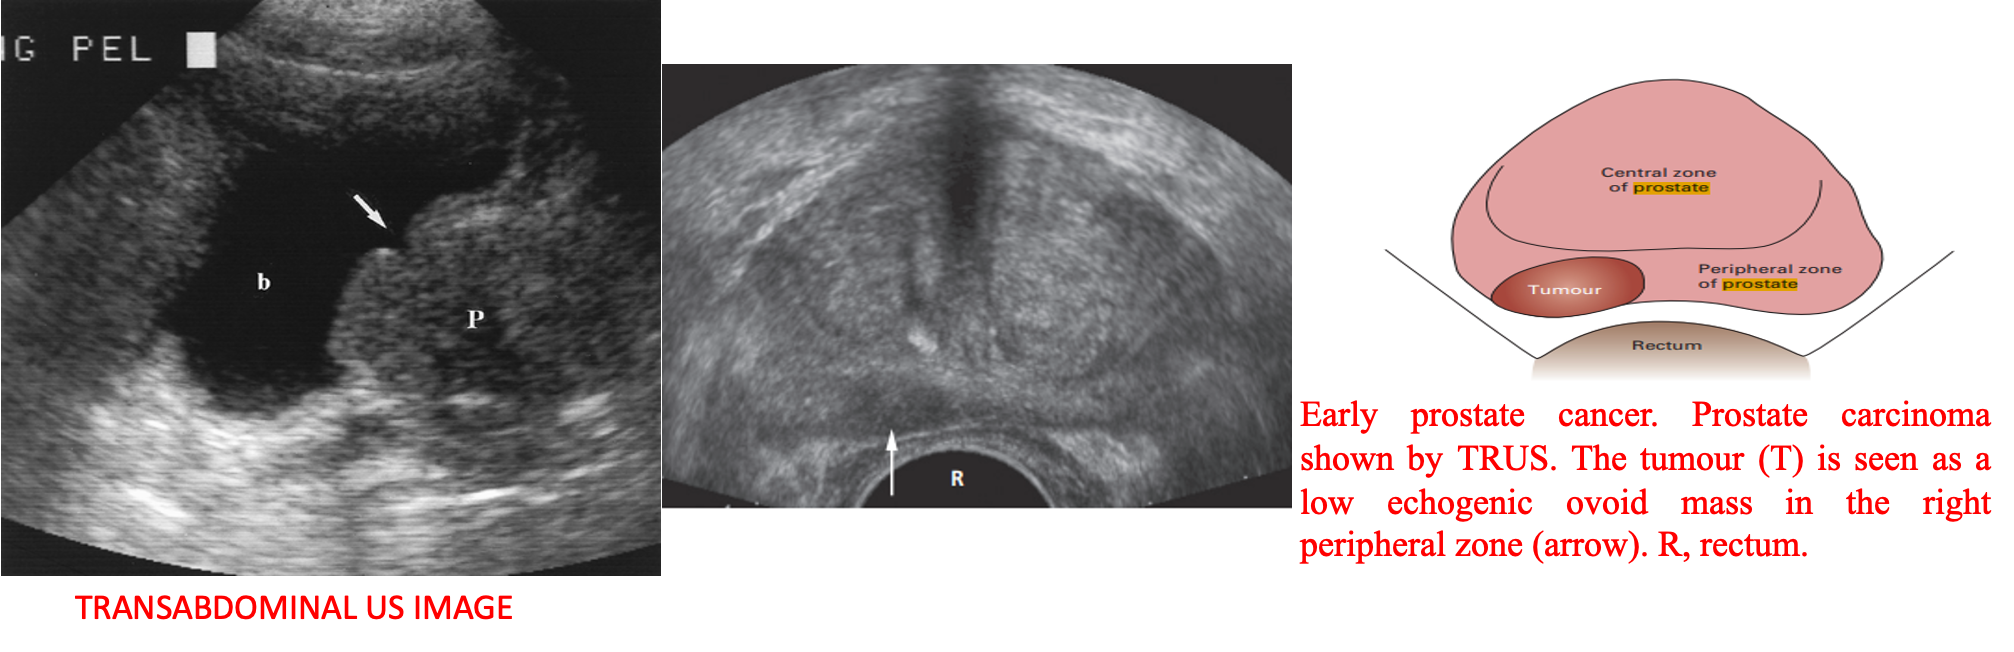

Ultrasound

cannot distinguish benign from malignant disease when confined to the prostate, except on the basis that masses in the peripheral zone are likely to be malignant and those in the central zone are more likely to be benign.

Transrectal ultrasound (TRUS)

Can show the overall size of the prostate and can diagnose relatively small masses within its substance.

Predominantly used to guide prostate biopsy.